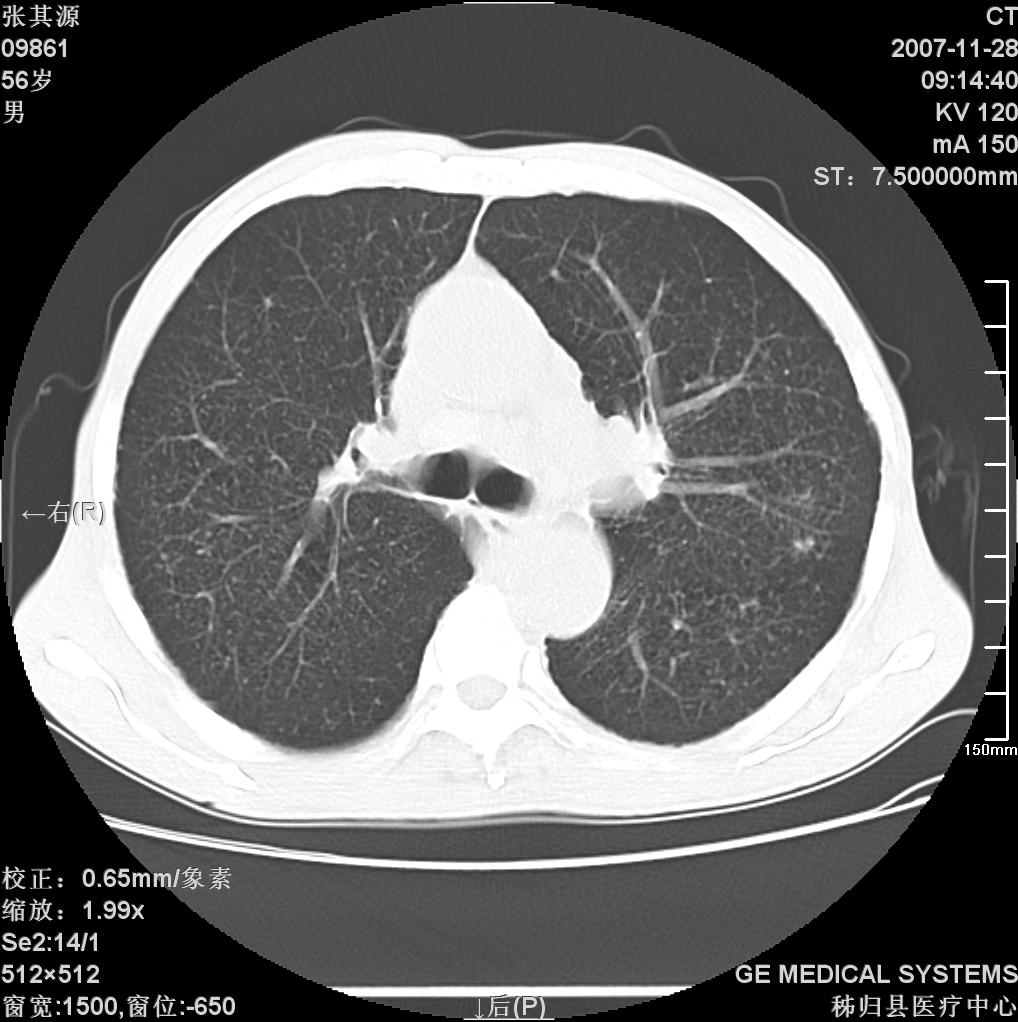

患者因阻塞性黄疸入院,发病前10天持续中等程度发烧.术前检查发现两肺弥漫性病变,请各位大虾会诊,除了考虑急性血源性肺结核外,还有其他什么疾病可能.

补充一下,该患者没有与尘肺相关职业史。请大家帮忙会诊一下,外科医生打算为其做胆总管肿瘤做手术的,现在在等我们的结果。谢谢各位了。

双肺多发粟粒样病灶,右肺胸膜下结节样病灶,气管前腔静脉后及隆突下均见肿大淋巴结,结合胆道肿瘤病史首先考虑转移。另外心影密度略低,时间格显示,是否有贫血?查明白再手术吧!